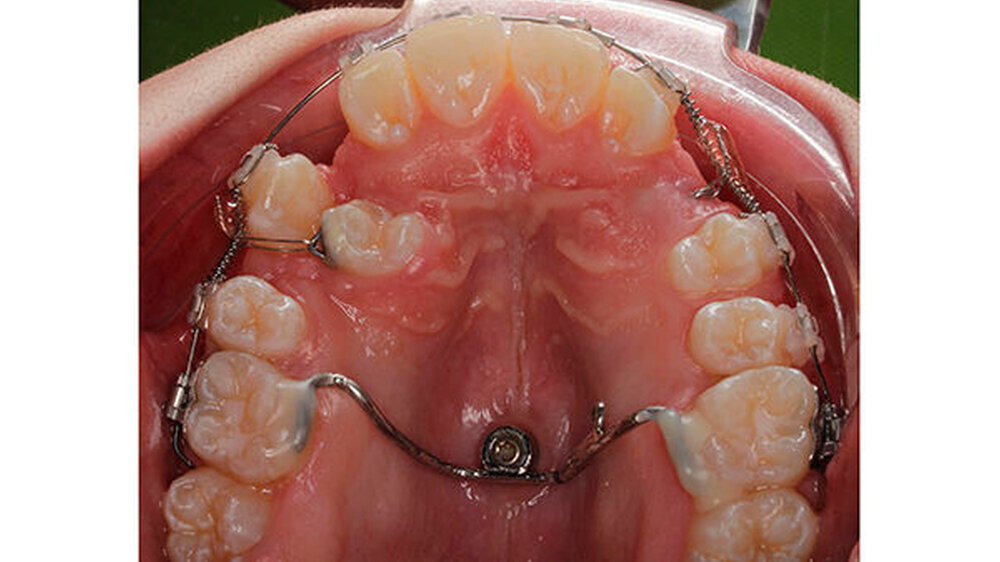

Zur Schaffung einer stabilen Verankerungseinheit wurde zunächst ein Gaumenimplantat inseriert und aufgrund des palatinal verlagerten Prämolaren 14 und des Eckzahns 23 im posterioren Gaumen platziert.

Ein mit dem Implantat verbundener Transpalatinalbogen, welcher adhäsiv an den Sechsjahresmolaren befestigt wurde, sollte letztere in ihrer Position stabilisieren und das während der Extrusion der verlagerten Zähne auf sie wirkende Drehmoment auffangen. Nach der Milchzahnextraktion und der chirurgischen Freilegung von Zahn 14 und 23 begann die kieferorthopädischen Einstellung der Zähne in den Zahnbogen mit geringen, kontinuierlich applizierten Kräften.

Im Laufe der Behandlung wurde Zahn 13 mesialisiert, um die Transposition mit Zahn 14 aufzulösen. Nachdem die Kronen der verlagerten Zähne soweit durchgebrochen waren, dass ein Bracket geklebt werden konnte, wurden sie mithilfe der Overlaybogentechnik in den Zahnbogen eingestellt. Die Wurzelaufrichtung des Zahn 14 fand mit einer Aufrichtefeder statt. Die restlichen Zähne wurden dabei mit einem 19 x 25 Stahlbogen stabilisiert.